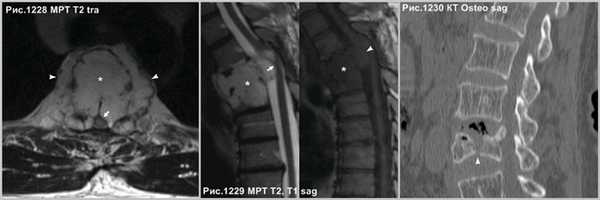

Осложнение в развитии гемангиом в виде экспансивного роста, что встречается не часто, когда опухоль (звёздочки на рис.1228,1229) распространяется за пределы тела позвонка (головки стрелок на рис.1228,1229), приводит к компрессии спинного мозга (стрелки на рис.1228, 1229). Серьёзное осложнение представляет собой патологический перелом тела позвонка (головки стрелки на рис.1230), структура которого была ослаблена разряжением губчатого вещества в процессе роста гемангиомы.

В случае нахождения гемангиомы в дужке или распространения с тела в дужку позвонка (головки стрелок на рис.1231-1233), важно указывать данный факт в связи с тем, что структура позвонка в указанном месте ослаблена и может послужить причиной патологического перелома в процессе медицинских манипуляций, так же важно учитывать этот факт нейрохирургам при транспедикулярной фиксации.